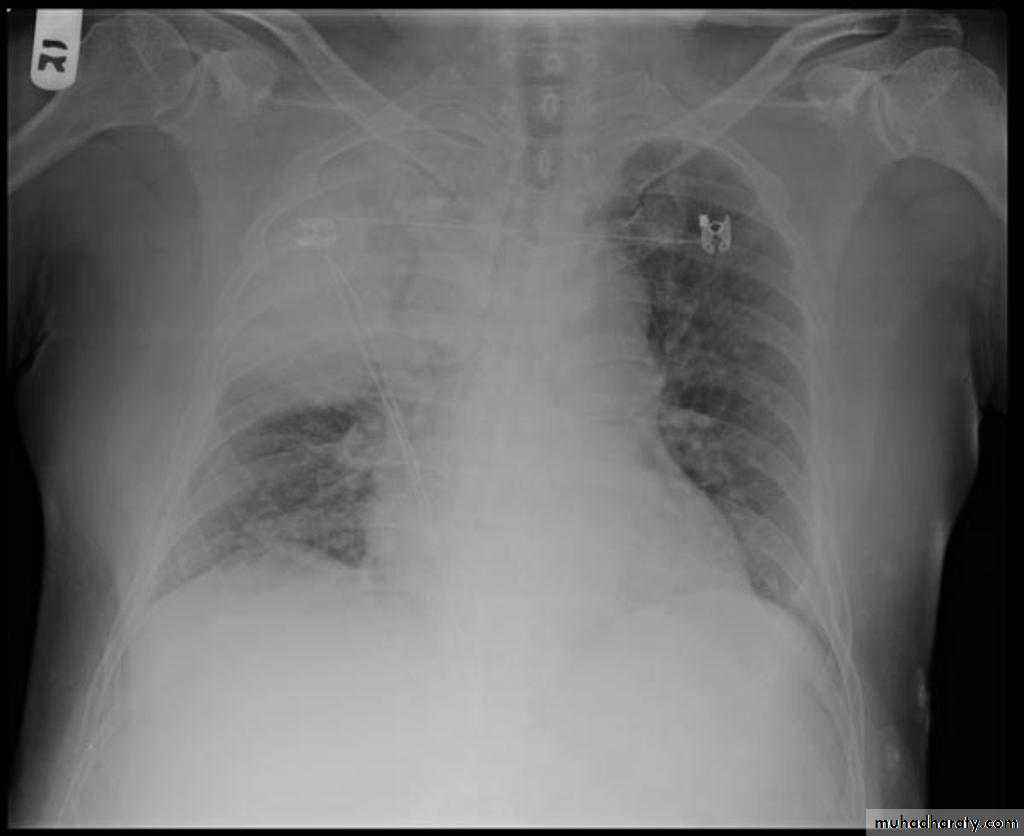

Hydro pneumothorax

58.hydropneumothorax